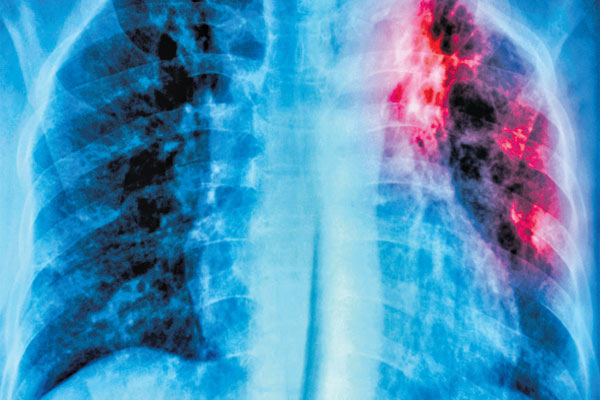

Tuberculosis or TB is an infectious disease that primarily affects the lungs. The bacteria usually spreads to people when an infected person sneezes or coughs which is why it is essential to timely diagnose TB and seek immediate medical attention. Let us take a look at how the disease can be treated in time…

TB infection happens owing to the bacteria Mycobacterium tuberculosis. It will take a toll on one’s lungs but can also impact other parts of one’s body along with the lymph glands, brain, kidneys, bowels, or bones.

The diagnosis of TB can be done by taking a sample of the mucous. A patient may be asked to go for sputum sample testing. Also, individuals may also be asked to undergo an X-ray, blood test, or even sputum smear microscopy to check prevalence of TB.